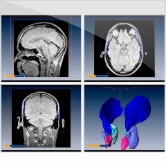

Brain in MNI Space

Surface views

Sections

3D reconstruction

BrainSlicer